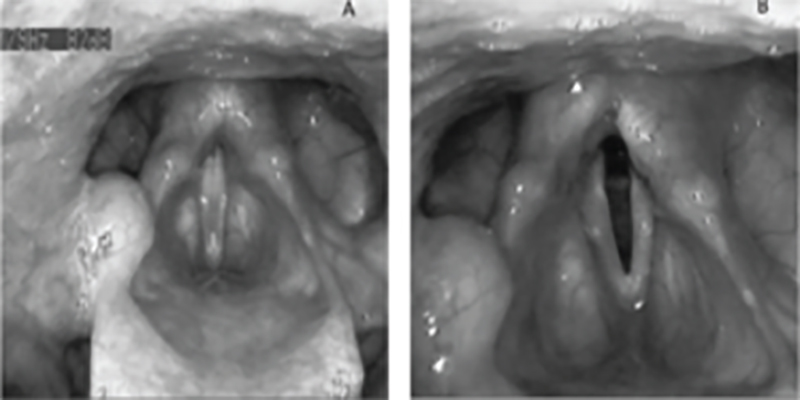

Μονόπλευρη Παράλυση Φωνητικών Χορδών

Η φωνοθεραπευτική παρέμβαση με την προσέγγιση IVT σε περιπτώσεις μονόπλευρης πάρεσης / παράλυσης φωνητικών χορδών στοχεύει στην ολική αποκατάσταση της φωνής, έστω και αν το νεύρο δεν επανέλθει ποτέ..

Αμφοτερόπλευρη Παράλυση Φωνητικών Χορδών

Τα κύρια συμπτώματα της αμφοτερόπλευρης παράλησης είναι αίσθηση ανεπαρκούς αναπανευστικής ικανότητας και, ανάλογα με τη θέση των καθηλωμένων χορδών, επηρεασμένη λιγότερο ή περισσότερο η ποιότητα της φωνής. Συχνά υπάρχουν δυσκολίες κατάποσης, συντονισμού στο βήχα, κόπωση και δυσκολία χρωματισμού της φωνής.